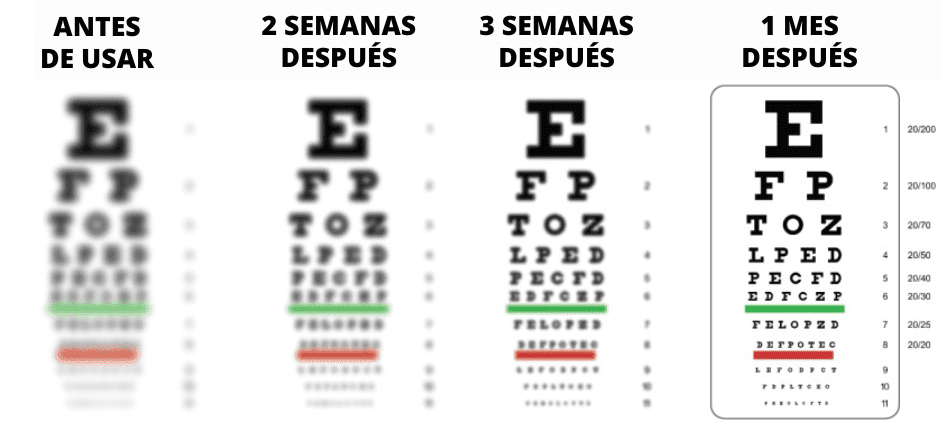

¿Cómo cambiará tu visión con Vizinex?

Desliza con el dedo para ver el resultado: